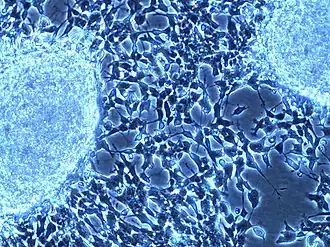

Microscopic view of stroma-rich ganglioneuroblastoma

On microscopy, the tumor cells are typically described as small, round and blue, and rosette patterns (Homer Wright pseudorosettes) may be seen. Homer Wright pseudorosettes are tumor cells around the neuropil, not to be confused with a true rosettes, which are tumor cells around an empty lumen.[29] They are also distinct from the pseudorosettes of an ependymoma which consist of tumor cells with glial fibrillary acidic protein (GFAP)–positive processes tapering off toward a blood vessel (thus a combination of the two).[30] A variety of immunohistochemical stains are used by pathologists to distinguish neuroblastomas from histological mimics, such as rhabdomyosarcoma, Ewing's sarcoma, lymphoma and Wilms' tumor.[31]

Neuroblastoma is one of the peripheral neuroblastic tumors (pNTs) that have similar origins and show a wide pattern of differentiation ranging from benign ganglioneuroma to stroma-rich ganglioneuroblastoma with neuroblastic cells intermixed or in nodules, to highly malignant neuroblastoma. This distinction in the pre-treatment tumor pathology is an important prognostic factor, along with age and mitosis-karyorrhexis index (MKI). This pathology classification system (the Shimada system) describes "favorable" and "unfavorable" tumors by the International Neuroblastoma Pathology Committee (INPC) which was established in 1999 and revised in 2003.[32]

Microscopic view of a NB cell line (SH-SY5Y) used in preclinical research for testing new agents